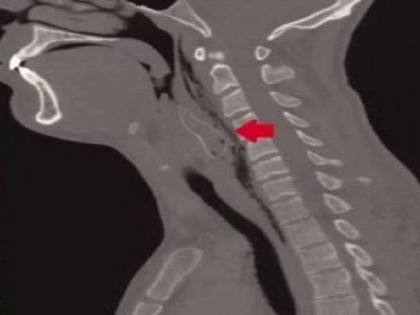

(प्रातिनिधीक छायाचित्र)

AajTak ने दिलेल्या वृत्तानुसार, तामिळनाडूच्या होसुरमध्ये एका तरूण तलावात मासे पकडायला गेला होता. तिथे त्याला जिवंत मासा गिळंकृत करतानाचा व्हिडीओ करण्याची आयडिया आली. व्हिडीओ शूट करताना तो मासा गिळंकृत करत होता आणि याच दरम्यान मासा तरूणाच्या घशात अडकला.

मासा घशात अडकल्याने त्याला श्वास घेण्यास त्रास होऊ लागला होता. जेणेकरून मासा निघेल म्हणून त्याच्या मित्राने त्याला पोटावर झोपवलं. पण त्याचा काहीही फायदा झाला नाही.